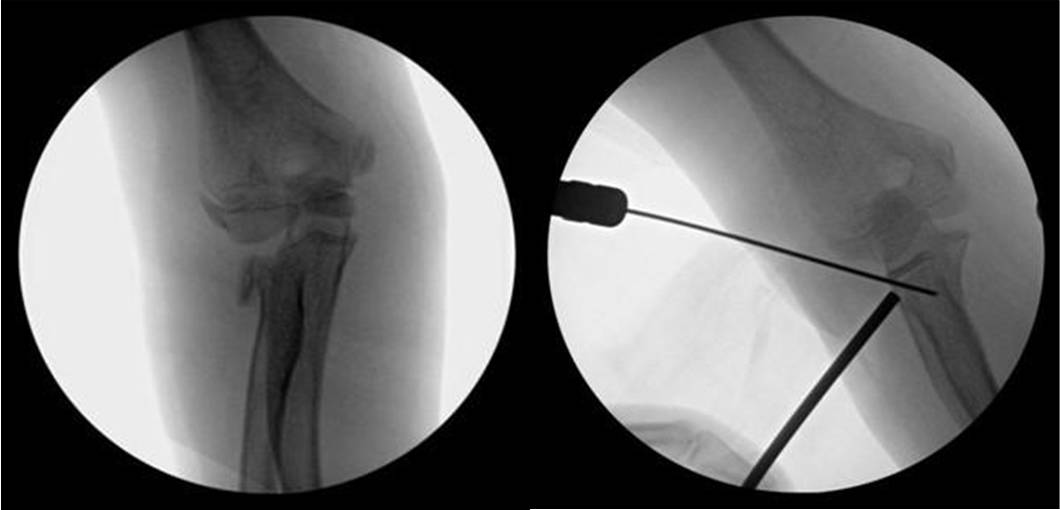

经外侧入路进行肘关节造影术的进针点及进针方向,解剖标志 1- 肱骨外侧髁,2- 桡骨头,3- 尺骨鹰嘴

6 岁患者发生 Monteggia 骨折,肘关节造影术术中前后位透视可见经闭合复位后的桡骨颈骨折(白色箭头)和尺骨鹰嘴骨折

7 岁患者发生桡骨颈移位性骨折,肘关节造影术术中前后位透视可见关节线,并可帮助骨折获得满意复位(造影相关文字及图片摘引:Nowicki 关节造影术在小儿骨科的应用.林超文译)